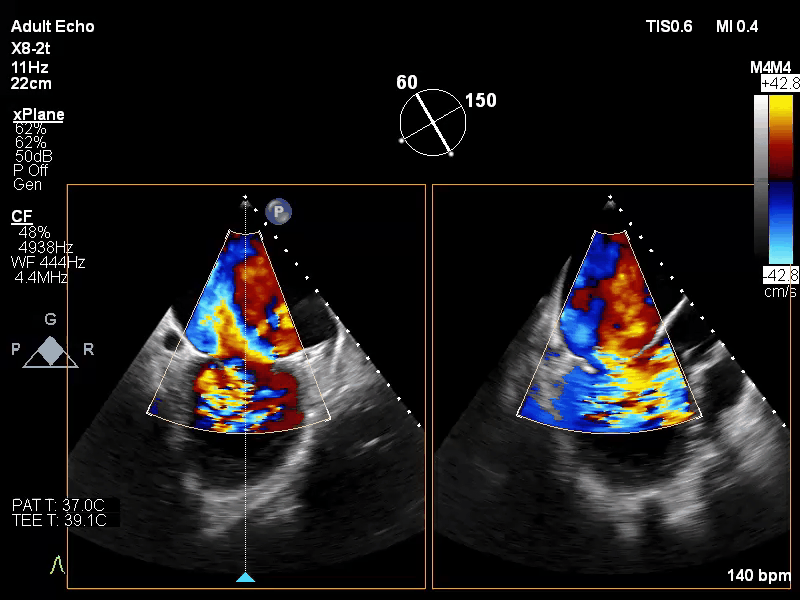

手术过程:

手术于全麻下进行,采用股静脉房间隔途径,房间隔穿刺后置入外径22F导管鞘及夹合器输送系统,在TEE引导下,将1枚长宽型号的KoKaClip®夹合器顺利植入到二尖瓣2区,夹合器位置稳定。彩色多普勒超声未见明显残余反流,肺静脉多普勒波形由反向恢复正常。多切面证实夹合组织充分,双孔化形成,遂移除器械输送系统,移除后夹合器活动度小,手术顺利完成,患者已于近日出院,出院超声复查良好。

术前

术后